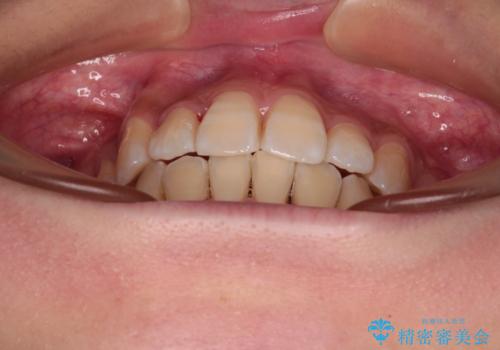

- 前歯のデコボコやクロスバイトと上顎の前突感による口の閉じにくさを気にして来院された患者様です。

目立たない装置を希望されたので、上顎が裏側装置のハーフリンガルを選択し、上下左右の小臼歯(計4歯)を抜歯して矯正治療を行うこととしました。

表側のワイヤー矯正に比べると治療期間は長く、費用も高額となりますが、どうしても目立たせたくないという方にはお勧めの抜歯矯正です。